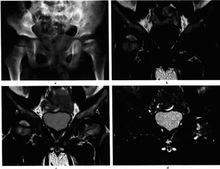

左股骨頭骨骺缺血性壞死(進展期)圖9-6左股骨頭骨骺缺血性壞死(進展期)

。雙髖正位平片,左股骨頭骨骺變扁,密度均勻增高,骨紋消失,骺線不規則增寬,乾骺部稍增粗變短;b.MRI冠狀位T1Wl;c T2Wl;d T2Wl抑脂像,示左股骨頭骺變扁,並呈長T1短T2信號改變,乾骺端內側近骺板處見不規則長T1、長T2 異常信號,抑脂像顯示乾骺端水腫,關節囊少量積液